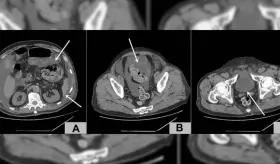

La gota es una enfermedad sistémica que puede afectar diferentes partes del cuerpo debido a la acumulación de urato monosódico en los tejidos.